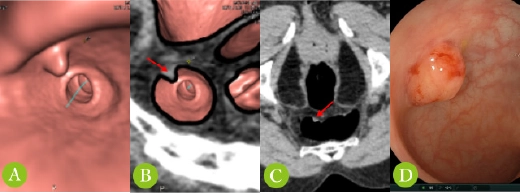

大腸CTC検査の実際例

(60歳代、女性、便潜血を指摘され精査目的で実施)

大腸CTC検査では3D構成画像(画像A)だけでなく、様々に条件を変更して構成した画像(画像BおよびC)を使用して診断します(腫瘍は赤矢印部分)。この検査例では、直腸内に隆起性病変がありポリープが疑われ、大腸内視鏡検査(画像D)を実施し、ポリープ切除術を施行しております。